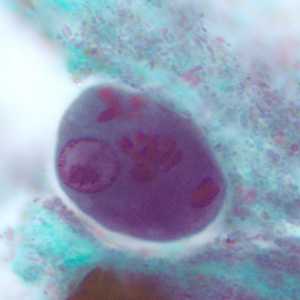

E. polecki cysts stained with trichrome.

Figure A: Cyst of E. polecki stained with trichrome. Notice the large nucleus with a pleomorphic karyosome and numerous variably-shaped chromatoid bodies.

Figure B: Cyst of E. polecki stained with trichrome. Notice the large nucleus with a pleomorphic karyosome and numerous variably-shaped chromatoid bodies.

Figure C: Cyst of E. polecki stained with trichrome. Notice the large nucleus with a pleomorphic karyosome and numerous variably-shaped chromatoid bodies.

Figure D: Cyst of E. polecki stained with trichrome. Notice the large nucleus with a pleomorphic karyosome and numerous variably-shaped chromatoid bodies.

Figure E: Cyst of E. polecki stained with trichrome. Notice the large nucleus with a pleomorphic karyosome and numerous variably-shaped chromatoid bodies.

Figure F: Cyst of E. polecki stained with trichrome. Notice the large nucleus with a pleomorphic karyosome and numerous variably-shaped chromatoid bodies.